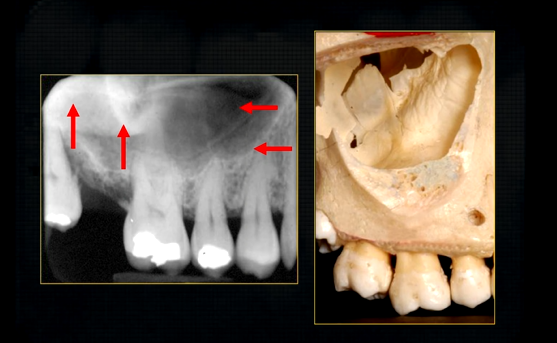

edentulous patient

can see u shaped edge of hollowed out zygomatic bone

periapical radiograph → posterior maxilla

radiolucent maxillary sinus and radiopaque floor

radiopaque shadow cast by zygoma, hollowed out by maxillary sinus

lower end of the dense, zygomatic bone

posterior aspect of the maxilla - smooth round tuberosity

bulk/prominence of the zygomatic cheekbone - radiographically this can overly the apical tissues of the upper molar teeth - solid, dense, white shadow

if its hollowed out by the maxillary sinus, it casts a white, radiopaque U shaped shadow - radiolucent centre